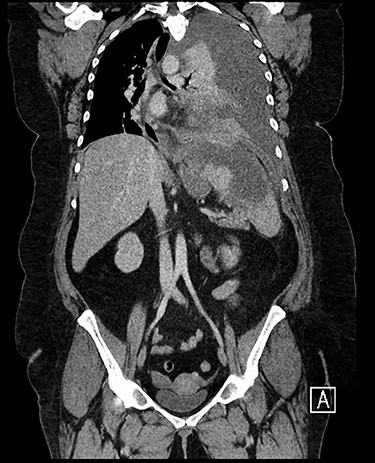

Forty-four-year-old clinically obese woman whose only past medical history was mild asthma with no use of systemic steroids. Initially presented with parapneumocic effusion following a recent bout of pneumonia which was not amenable to aspiration. Prior to this, the patient had experienced vague abdominal symptoms 1 month prior to the onset of the pneumonia. She was treated with oral amoxicillin. Twenty-five days later, she presented again in the Accident & Emergency Department with left-sided chest pain, left flank pain associated with fever and worsening dyspnea. Computed tomography (CT) scan (Fig. 1) showed a significant left-sided effusion with a complete collapse of the left lung and mild mediastinal shift towards the right. A 12.5 cm collection in the upper pole of the spleen was noted which appeared to extend through the diaphragm (Fig. 2). She was started on the sepsis pathway as per hospital protocol. A seldinger chest drain was inserted which immediately drained 1500 ml of pus. She underwent a thoracoscopic washout, debridement and decortication. The chest drains were removed 9 days post-operatively. She was transferred to General surgeons where a percutaneous drain (pigtail catheter) was inserted under ultrasound guidance. Three hundred and five milliliters in a total of pus was drained from the splenic abscess. Staphylococcus aureus was isolated from both the pleural and splenic collection. Blood cultures and transthoracic echocardiogram were unrevealing. A blood bourne virus screen (Hepatitis B, Hepatitis C, HIV) was negative as well. A repeat ultrasound scan showed complete resolution of the splenic abscess with normal splenic architecture.

CT chest, abdomen and pelvis coronal view: left-sided empyema and splenic abscess.